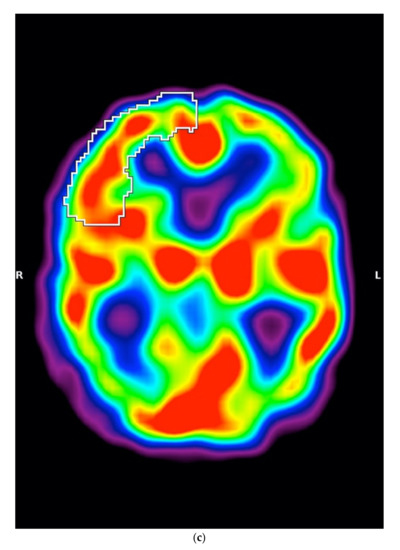

5.1.3. SPECT

In SPECT imaging, patients with MSA-P had higher regional cerebral blood flow in the right frontal lobe (p = 0.0012) (Figure 2a–c).

Figure 2.

(a) Scatterplot presenting the significant differences between MSA-P and PSP-P in the right frontal lobe, (b) Axial 99mTc-HMPAO SPECT of a patient with PSP-P (frontal lobe hypoperfusion), (c) Axial 99mTc-HMPAO SPECT of a patient with MSA-P (without frontal lobe hypoperfusion).

Previous studies demonstrated the role of MRI in the examination of the entities in the early years of the disease. In this study, the authors evaluated the period between 3 and 6 years duration, during which the entities could be expected to be potentially differentiable, using easily accessible cognitive assessment screening. This observation may be interpreted as coming to the same conclusions as the study conducted by Jecmenica-Lukic et al., where the authors showed a more beneficial course for PSP-P when compared with MSA-P [29]. The authors compared the differentiating potential of MMSE and MoCA with perfusion SPECT and MRI. The results show that among patients who cannot undergo MRI, an assessment of frontal perfusion may be a beneficial additional examination. The assessment of mesencephalon and M/P ratio is a feature described in various studies; however, frontal lobe perfusion evaluation has not been broadly evaluated in PSP-P. In this study, the authors used the Bonferroni correction; however, before using it, additional parameters showed significant differences (threshold below 0.05) between PSP-P and MSA-P. Among them could be mentioned the perfusion on the left frontal lobe (p = 0.0121), the perfusion of the right thalamus (p = 0.0314), the width of the third ventricle (p = 0.048) and the width of MCP (p = 0.0045). After implementing the Bonferroni correction, the significance in these regions was not maintained. The authors believe that the regions should be additionally verified in larger groups and interpreted as probably significantly differentiating (Table 1 and Table 2).